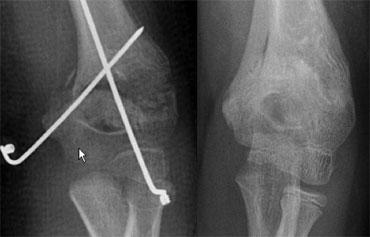

Gãy xương loại III theo Gartland là gãy xương di lệch hoàn toàn và có nguy cơ liền xương lệch và biến chứng thần kinh mạch máu (hình).

Những trường hợp này cần được nắn chỉnh bằng phương pháp kín hoặc nếu cần thiết bằng phương pháp mổ hở. Cố định được duy trì bằng hai đinh bên ngoài hoặc kỹ thuật đinh chéo trong-ngoài.

Gartland III fracture with medial-lateral cross pin technique. After reduction there is inadequate correction of medial collaps. After two months there is malunion with cubitus varus deformity.

Gãy xương trên lồi cầu (4)

Liền xương lệch sẽ dẫn đến biến dạng ‘báng súng’ điển hình do xoay hoặc không chỉnh đủ tình trạng sụp đổ phía trong.